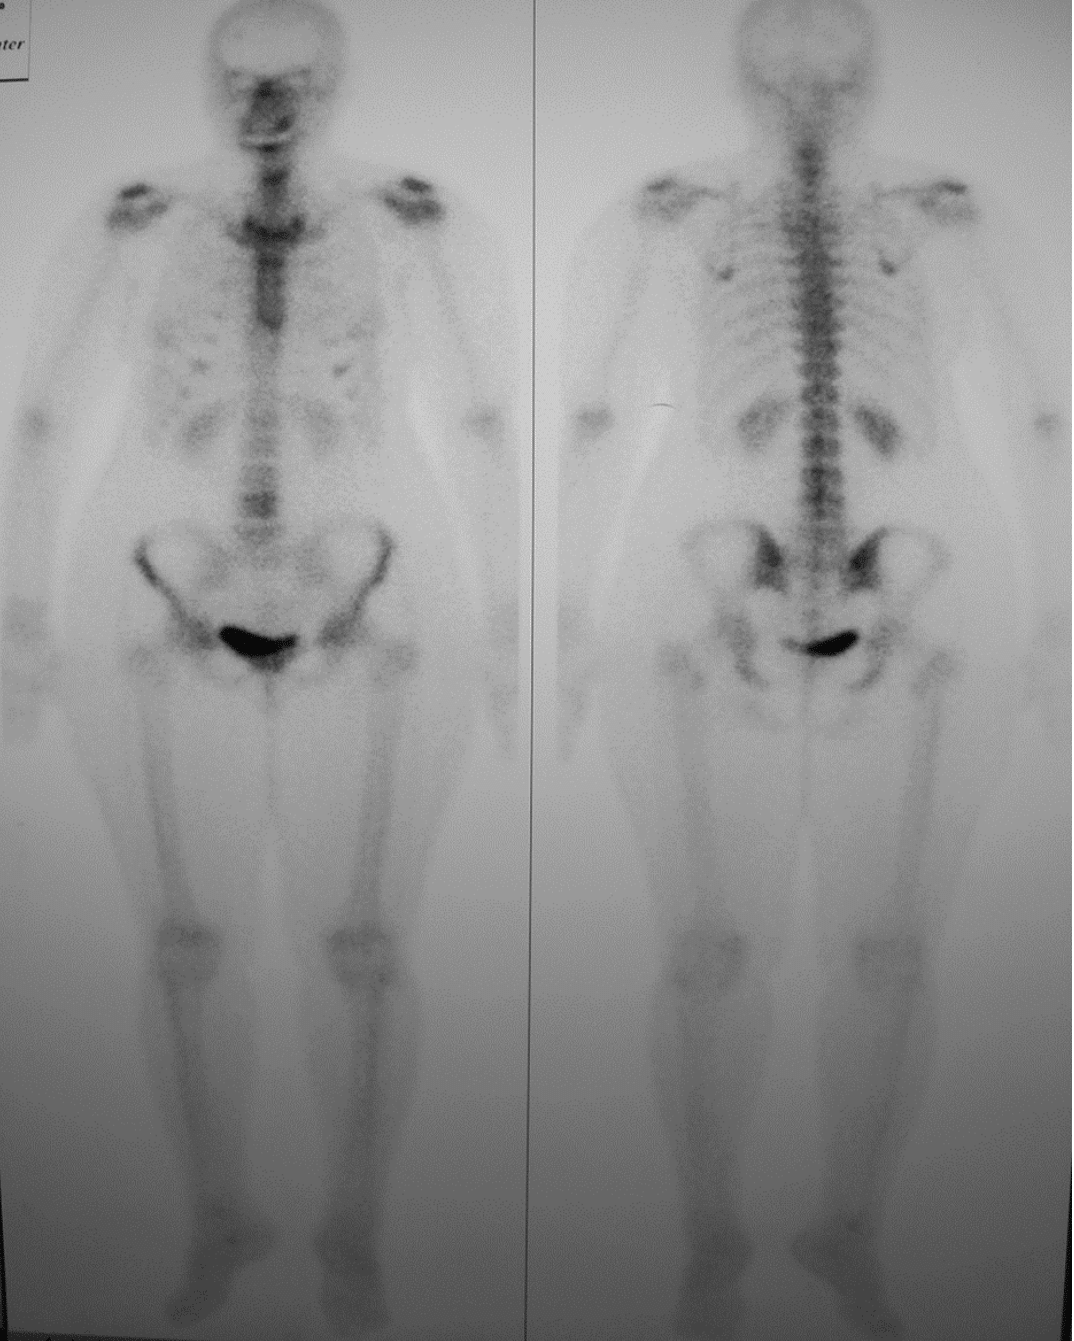

Preoperative radiographic examination including panoramic X-ray and C.T for evaluation of mandibular bone invasion by the lesion and evaluation of the neck lymph nodes (Figure 2A, B, C). Both the mandibular bone and neck lymph nodes were free. Whole body scan with Technetium-99m radiopharmaceuticals imaging was negative (Figure 2D). Clinical stage according to TNM system was T1N0M0.

Figure 2d Negative whole body scan with Technetium 99.